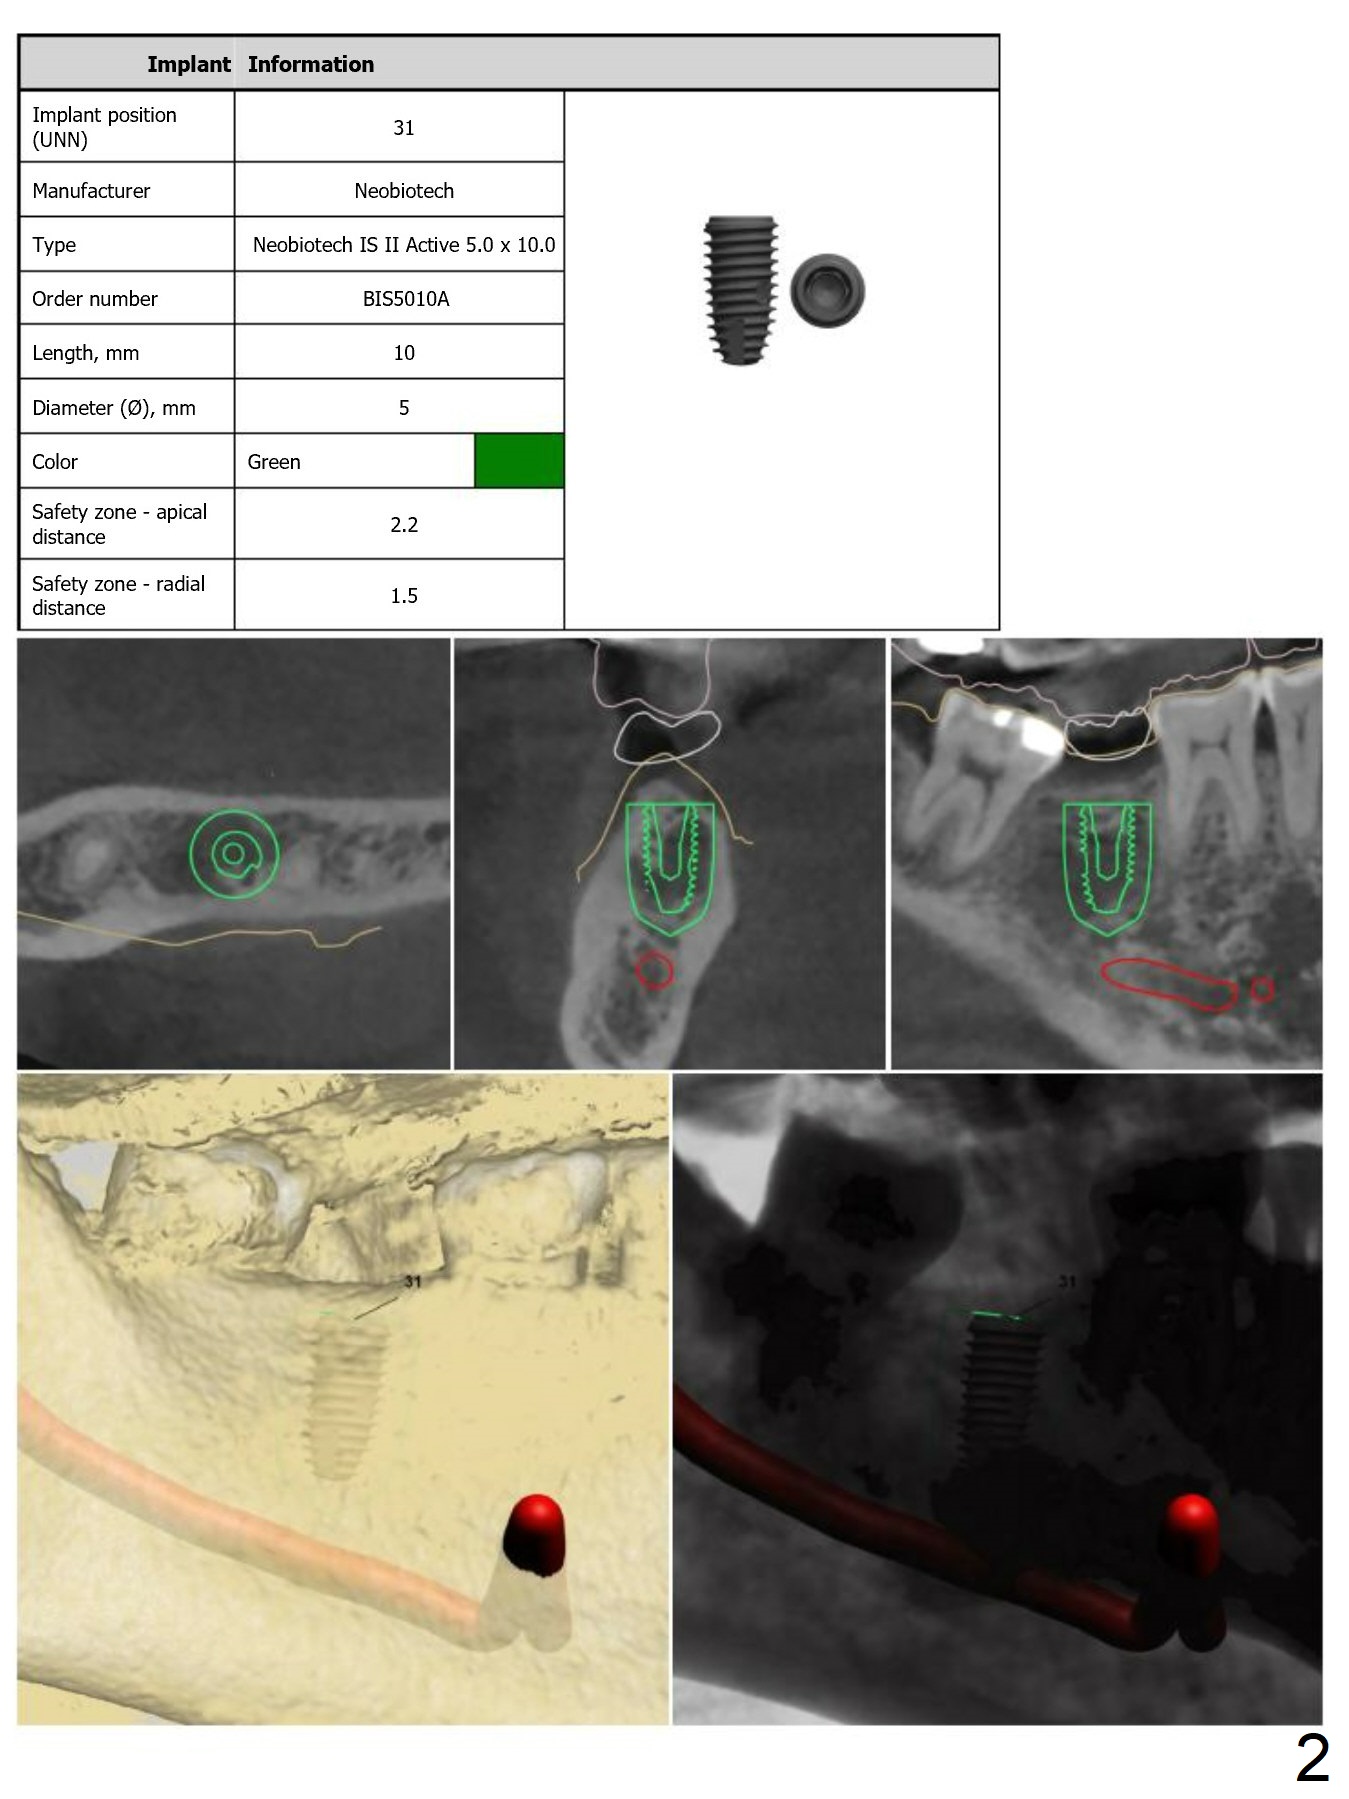

Guide for #31 Placement